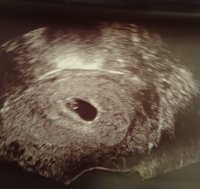

Så godt å se livVar på tidlig uktralyd i dag. Skulle ha vært 6+6, men spiren målte kun 6+3. 58 mm målte lille. Kunne se at hjerte slo, men fikk ikke høre.

Noen andre som har opplevd å bli satt tilbake? Blir litt stresset over det. Vis vedlegget 362074